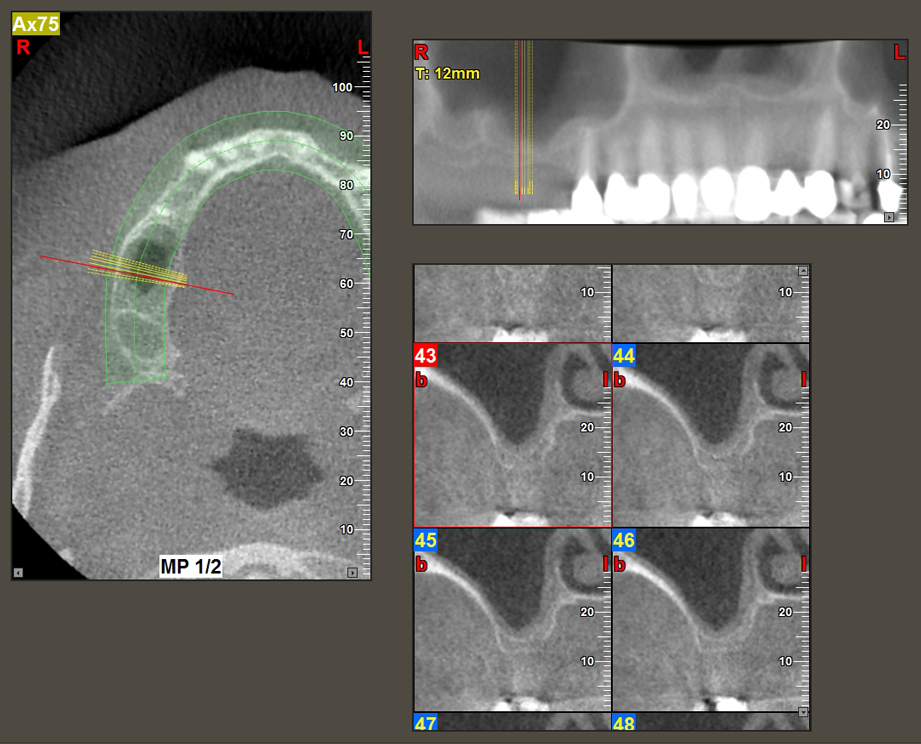

Una paziente di 49 anni, non fumatrice e con un'anamnesi priva di elementi rilevanti, è stata indirizzata al nostro studio di chirurgia orale per l'estrazione chirurgica del dente 16 ed il successivo impianto. Dopo l'estrazione, la paziente ha accusato dei lievi dolori causati dalla sinusite, motivo per cui abbiamo inizialmente aspettato sei mesi prima di procedere con l'intervento. L'altezza ossea residua in corrispondenza della posizione dell'impianto misurava 3-4 mm (Fig. 1 e 2).

Fig.2: il DVT mostra le corrette dimensioni in ogni vista assiale (sinistra), laterale (in alto) e trasversale (destra). La membrana del seno mascellare è ancora leggermente ispessita.